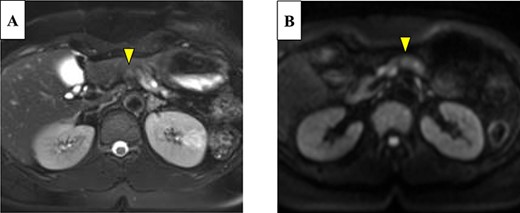

Abdominal-enhanced computed tomography (CT) revealed a low-density pancreatic body tumor of 25 mm in diameter, which was close to the gastroduodenal artery (GDA), and was accompanied by atrophy of the distal pancreatic parenchyma and dilation of the upstream MPD (Fig. 1A). Moreover, CT imaging of the portal phase revealed a filling defect within the splenic vein where it was in contact with the tumor (Fig. 1B). On magnetic resonance imaging, the tumor appeared as an area of signal hyperintensity on T2-weighted and diffusion-weighted images (Fig. 2A and B). On positron emission tomography-CT scan, the tumor exhibited greater uptake of 18F-fluorodeoxyglucose (Fig. 3). Although a definitive preoperative diagnosis could not be made, we suspected pancreatic ductal adenocarcinoma, and distal pancreatectomy with lymph node dissection was scheduled, without neoadjuvant chemotherapy, after obtaining consent from the patient. The pancreas was divided along the left edge of the GDA after mobilization of the artery; however, pathological examination of a frozen section of the pancreas stump was positive for PNET, and therefore a total pancreatectomy was performed (Fig. 4). The duration of surgery was 610 min, the intraoperative blood loss was 195 mL, and blood transfusion was not performed.

On magnetic resonance imaging, the pancreatic tumor is shown as a hyperintense area in T2- (A) and (B) diffusion-weighted images (yellow arrows).